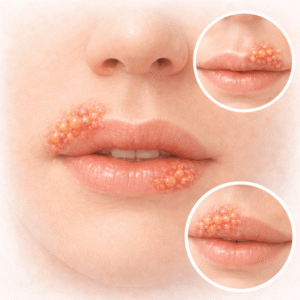

Herpes

Ymmärtäminen Herpes Herpes on erittäin tarttuva virusinfektio, jonka aiheuttaa herpes…